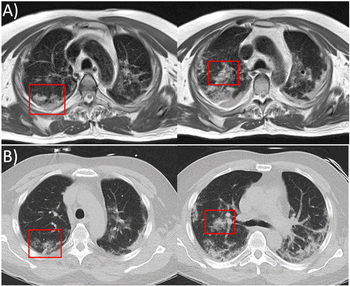

Six-month follow-up CT scans show lingering fibrotic-like feature in more than one-third of recovered patients.